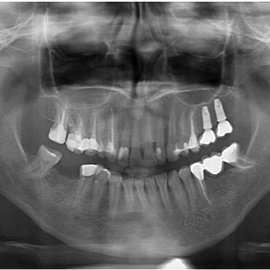

Lat 50, pół roku przed rozpoczęciem leczenia implantologicznego przestał palić papierosy. Znacząca poprawa higieny, pacjent silnie zmotywowany. Po regeneracji kości i rekonstrukcji tkanek miękkich odbudowa sześciu zębów na koronach porcelanowych. Na zdjęciu widoczna ilość i jakość tkanki kostnej po rekonstrukcji. W porównaniu ze stanem początkowym uzyskano znaczącą poprawę warunków kostnych nie do osiągnięcia metodami sterowanej regeneracji kości z użyciem reklamowanych markowych błon kolagenowych i dosypaniem kości z butelki.

Pacjent z długą historią leczenia implantologicznego. Pierwsze implanty w pozycjach 23, 24 miał wkręcane w Warszawie przed 25 laty. Implant w pozycji górnego prawego kła ma agresywny gwint, ponieważ bezpośrednio po implantacji był obciążony (immediate loading) tymczasowym atachmentem ball abutmentv do stabilizacji tymczasowej protezy ruchomej. Kość szczęki regenerowana i odbudowywana etapami w całym górnym prawym kwadrancie. Pacjent planuje uzupełnić brakujące zęby 25, 26.